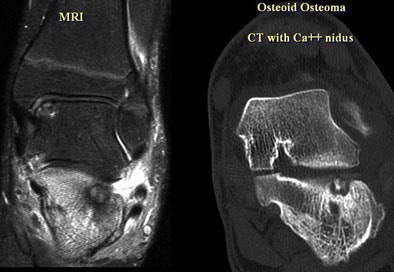

In an 18-year old presenting with foot pain, MRI showed diffuse marrow edema throughout the calcaneous on axial T1 and T2 MRI images, Gold said. But CT (0.5-mm reconstructions) was needed to adequately characterize the lesion, clearly showing a calcified nidus, Gold said. The diagnosis was osteoid osteoma of the subtalar joint.